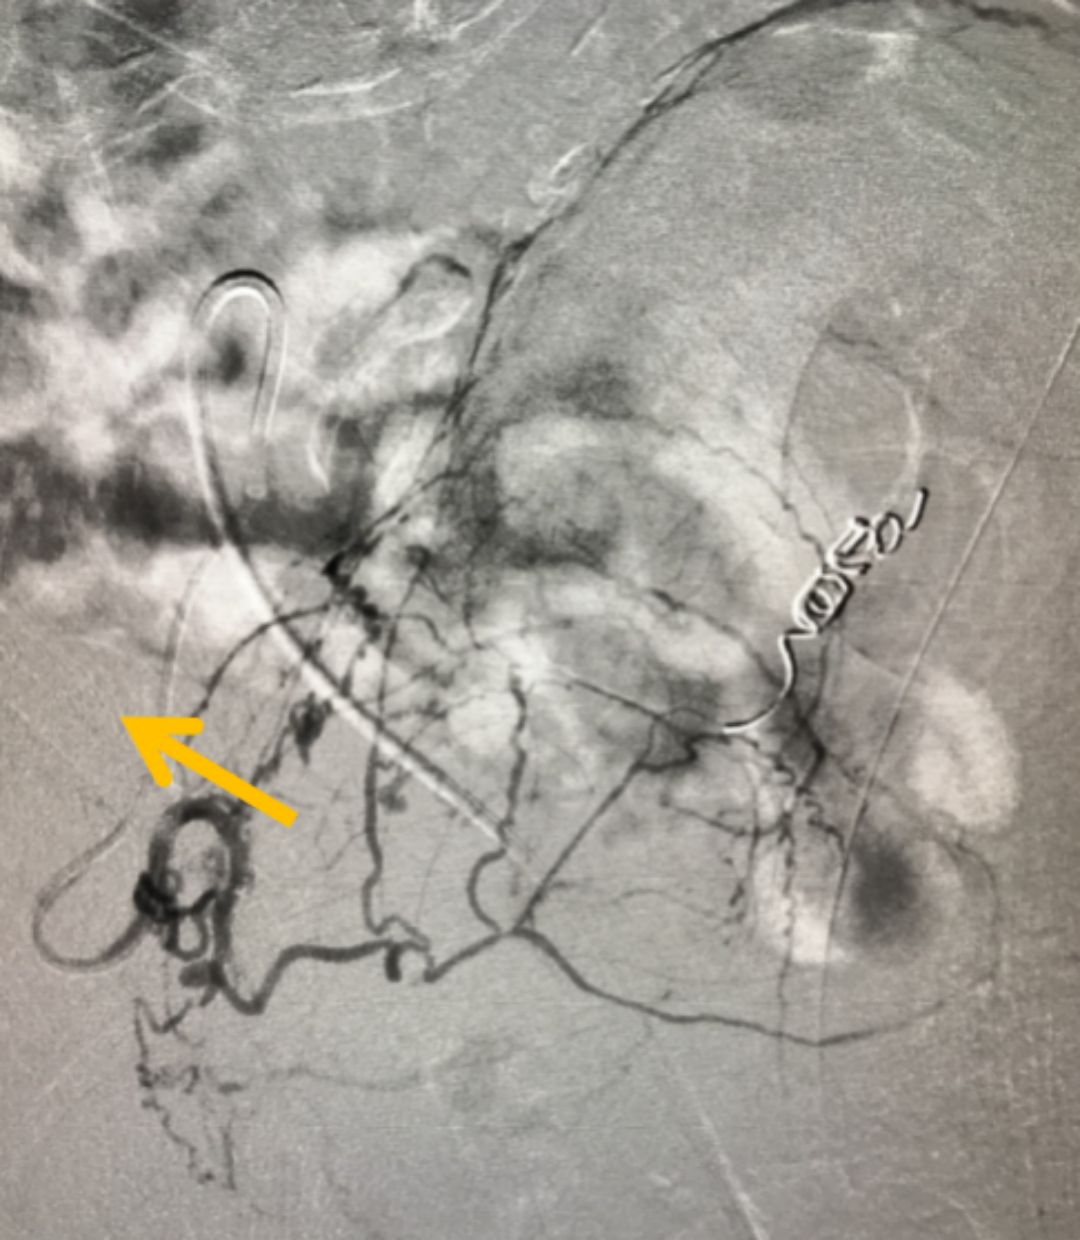

在全面評估后,團(tuán)隊(duì)為他制定了PAE的精準(zhǔn)治療方案。手術(shù)僅通過大腿根部一個針眼大小的穿刺點(diǎn),將比頭發(fā)絲還細(xì)的微導(dǎo)管,在影像引導(dǎo)下精準(zhǔn)送入供養(yǎng)前列腺的動脈,并注入安全的栓塞微粒。這個過程,就像精準(zhǔn)地“斷糧”

圖:微導(dǎo)管(箭頭所指)

增生的前列腺組織需要充足的血液供應(yīng)才能維持“生長”。PAE技術(shù)的核心,就是阻斷這些供給增生的“營養(yǎng)通道”,從而讓過度增殖的組織因“饑餓”而自然萎縮、壞死,解除對尿道的壓迫。